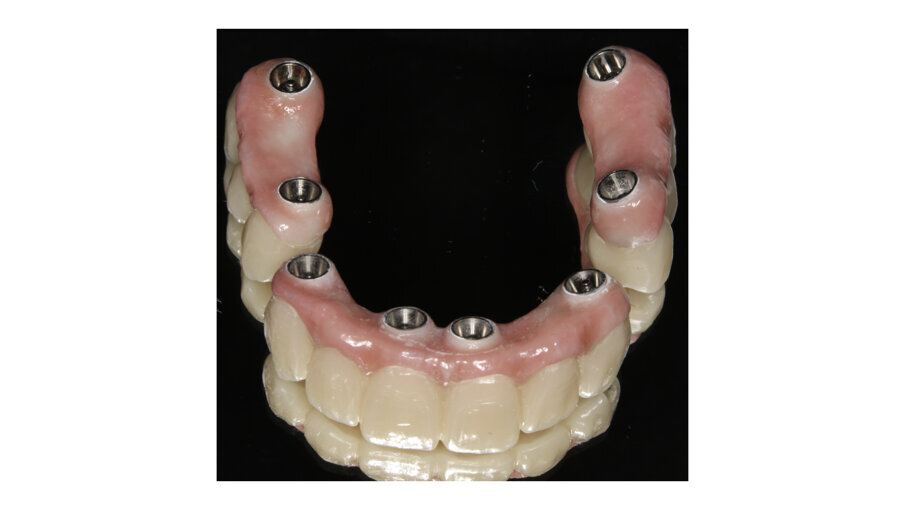

Another common situation is a full mouth restoration over implant. It is well known that the big issue is chipping and delimitation of the ceramics, due to the high forces applied in the patient with dental implants. In regards to this problem, the combination of rigid materials to support the connectors and resilient materials to absorb the shock and, at the same time, allow easy fixation, make the use of resin based blocks the logical choice for this kind of restoration (Figs. 6-8).

Fig. 6: Zirconia thimble framework and BRILLIANT Crios bridges for extra oral bonding.

Fig. 7: Zirconia bridges ready to be screwed.

Fig. 8: Upper and lower bridges in the mouth.

Fig. 9: Panoramic view of the finished case.